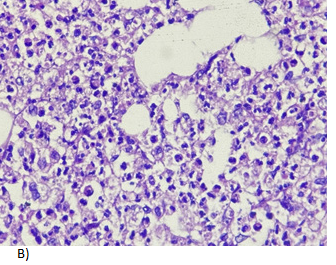

A 27-year-old male with a history of multiple hospitalizations and transfusions for dengue hemorrhagic fever, HIV (+) seven years ago with self-suspended treatment five months ago. He went to the emergency room due to abdominal pain in the epigastrium of three weeks' evolution accompanied by hyporexia, asthenia, and adynamia with hematochezia on one occasion, vomiting coffee grounds on one occasion with respiratory difficulty and dyspnea, denying fever or cough. Physical examination revealed moderate dehydration, pale integuments, tachypnea, and wheezing in the left hemithorax with wheezing in the right hemithorax, abdomen with signs of peritoneal irritation, vital signs: BP 100/60 mmHg, HR 154/min, Breaths 28/min, temp. 36.8 °C. Diagnosis of probable community-acquired pneumonia plus upper gastrointestinal bleeding, severe dehydration and HIV, hypovolemic shock, and septic shock are included. Laboratories: hemoglobin 5.5g/dL, leukocytosis (31000/103/L, absolute neutrophils 28 302/103L, lactic acidosis (PCO2 20.300 mmHg, PO2 73.40mmHg, HCO3 11.50mEq/L and lactate 12.60mmol/L). Tomography with data of honeycombing in both lungs to rule out PTB vs. PCP (Pulmonar tuberculosis vs. Probable Candida parapsilosis), left pleural effusion, bilateral atelectasis, and free peritoneal fluid with suspicion of probable gastric perforation. A CT scan is performed without specifying the origin of the septic shock (Figure 1 & 2). The patient is admitted to the operating room for exploratory laparotomy, purulent fluid (2500ml) is aspirated, a splenic abscess is identified on the diaphragmatic side and splenectomy is performed with the standard technique, admission to the Register Intensive Care Unit, later to the general surgery floor with an in-hospital stay of 9days, he is discharged with control by internal medicine, surgery and SAIH (Hospital Comprehensive Care Services).

Figure 1 Tomography showing a perisplenic collection of heterogeneous density with water and gas density, suggestive of splenic abscess and reactive perihepatic free fluid.